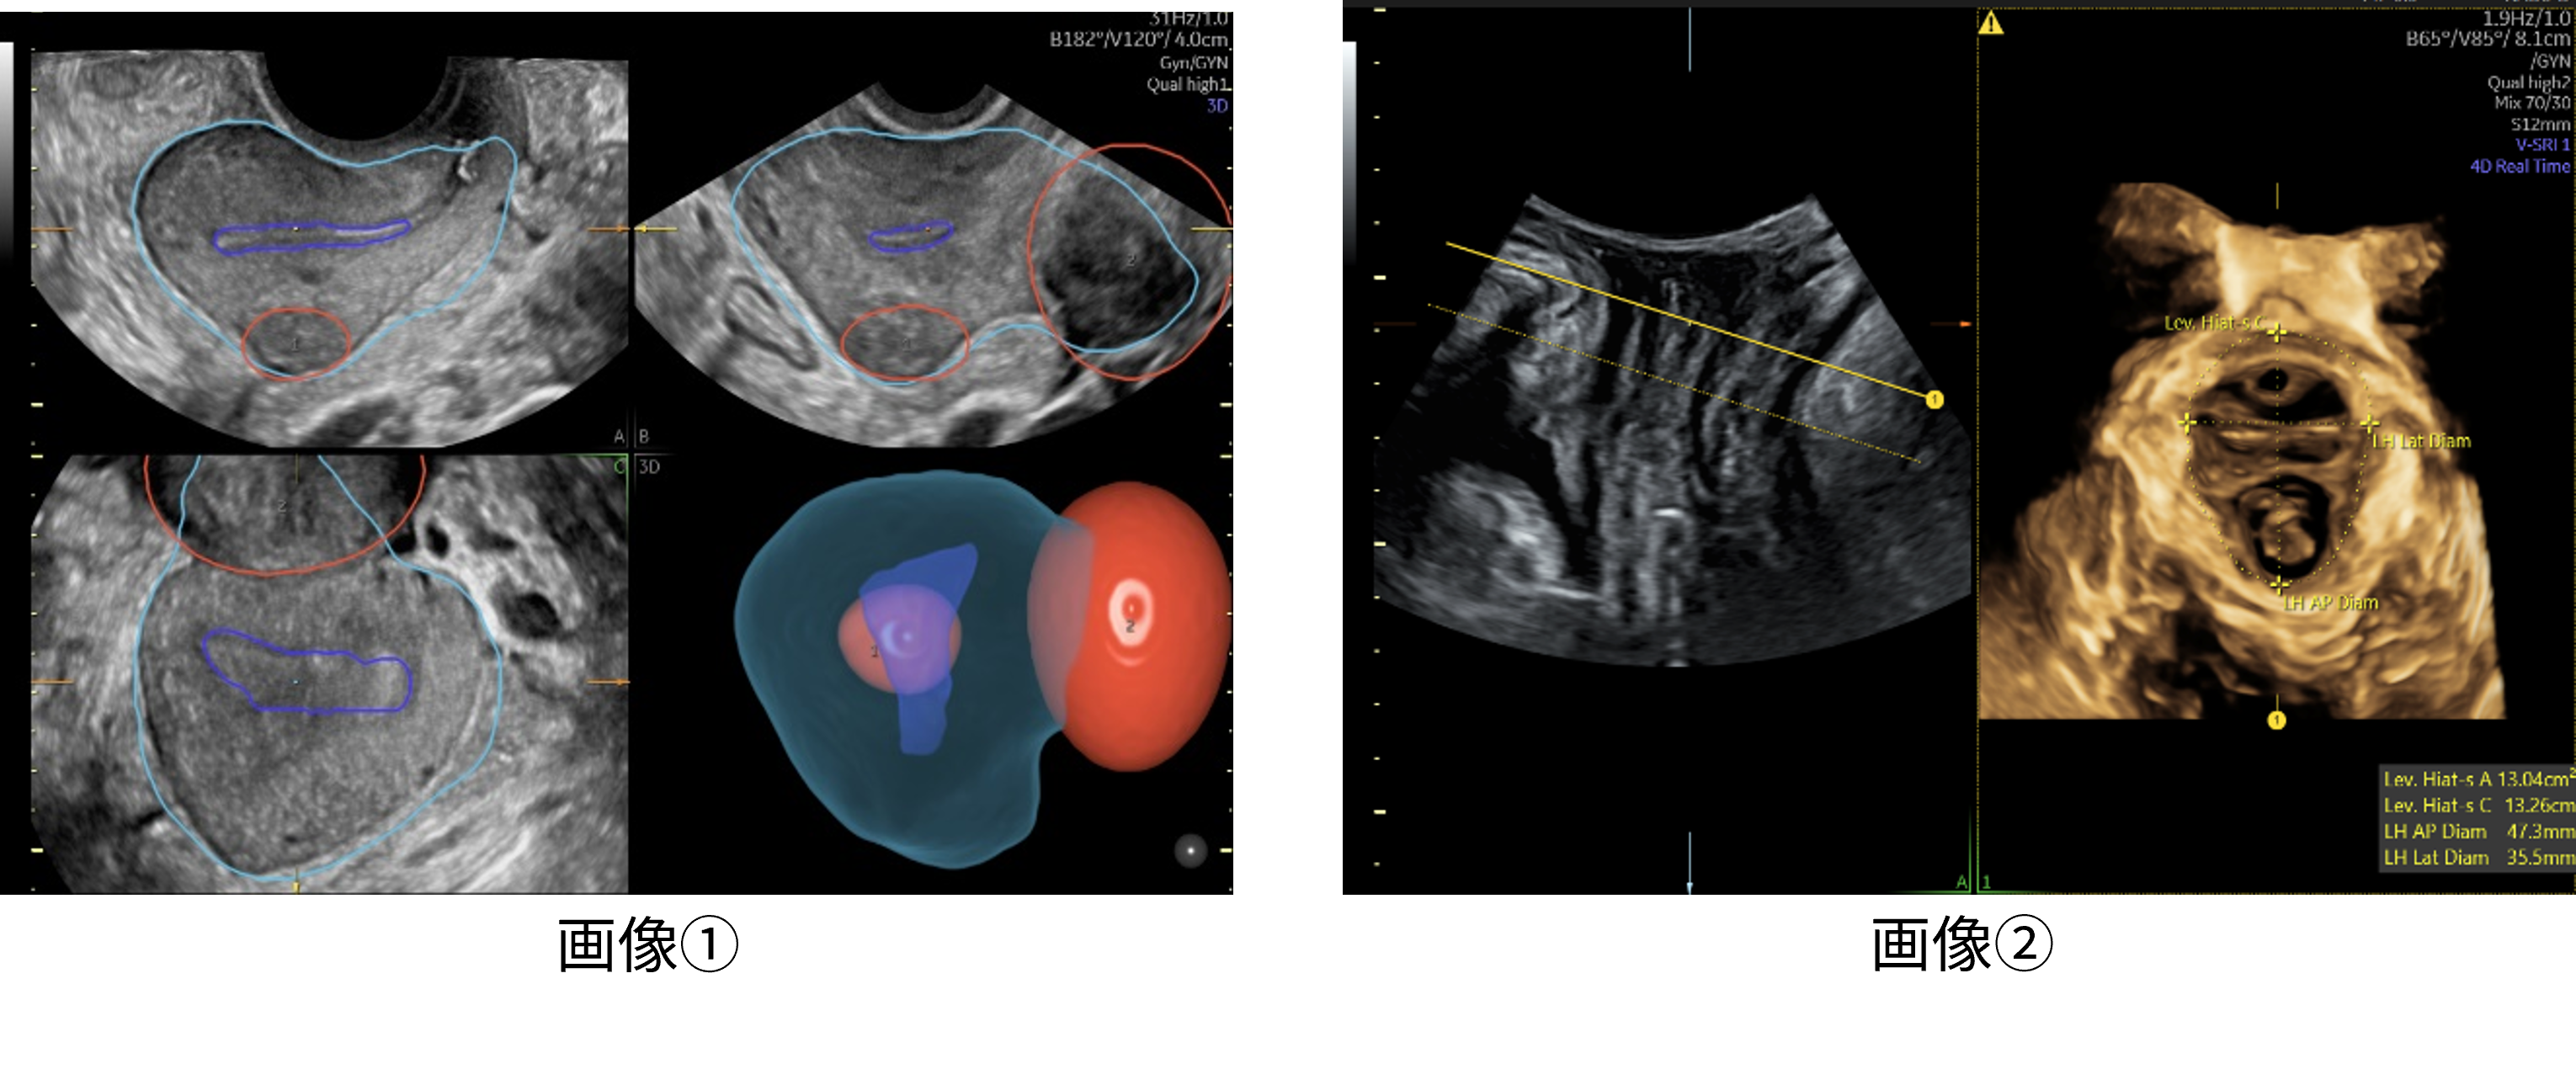

Volusonが長年培ってきた3D技術と、開発へのAI活用により、婦人科超音波検査の効率化に貢献する2つのアプリケーションを搭載しました。1つは、少ないステップで子宮筋腫の立体的位置関係を可視化する機能で、これまで断層像を用いて立体像をイメージしながら実施していた検査を3D画像化することで、簡便に子宮内膜との位置関係や、大きさを把握できるようサポートします。(画像➀)